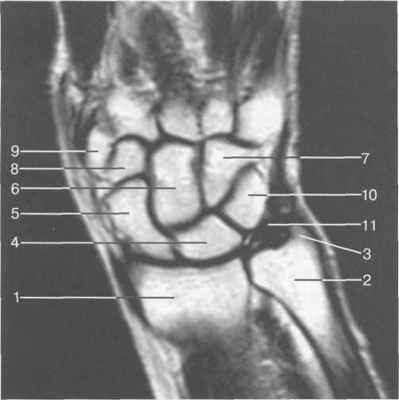

Рис. 19.53. МРТ лучезапястного сустава и костей запястья (корональная плоскость).

1 — лучевая кость; 2 — локтевая кость; 3 — шиловидный отросток локтевой кости; 4 — полулунная кость; 5 — ладьевидная кость; 6 — головчатая кость; 7 — крючковидная кость; 8 — трапециевидная кость; 9 — кость-трапеция; 10 — трехгранная кость; 11 —треугольный диск.